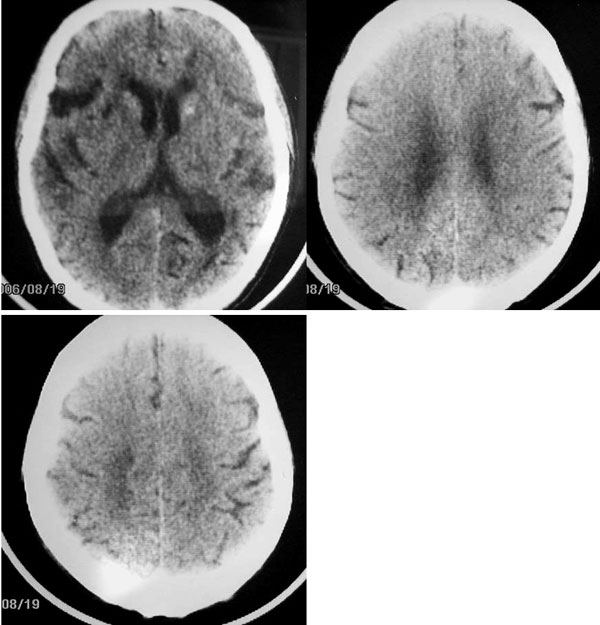

以下是引用卜一在2006-11-11 18:14:00的发言:[br]多发性腔梗,脑白质脱髓鞘变性,脑萎缩(老年性脑内三联征),考虑:皮层下动脉硬化性脑病.